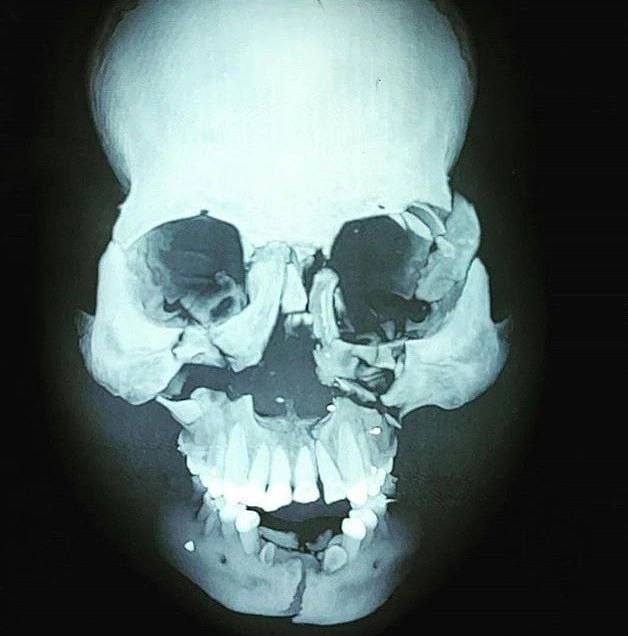

Раздробленный перелом лицевой части черепа